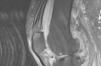

On physical examination, the patient was afebrile and stressed left knee monoarthritis with functional impotence for knee flexion. The rest of the examination found no significant alterations. Arthrocentesis was performed, yielding 4cm3 of liquid of inflammatory characteristics: 9650leukocytes/mm3 with a predominance of polymorphonuclear cells (94%) and glucose 75mg/dl. Monosodium urate crystals were observed under polarized light microscopy. Gram stain was negative. The synovial fluid culture was isolated Escherichia faecium (E. faecium) sensitive only to vancomycin. Laboratory tests showed no leukocytosis (8600/109 leukocytes, 60% neutrophils, 20% lymphocytes) but elevated acute phase reactants (ESR: 100mm in the first hour, C-reactive protein: 238mg/dl). Urine sediment was normal and blood and urine cultures negative. We completed the study with a chest X-ray and echocardiography to rule out pulmonary and/or cardiac affection. A simple X-ray of the left knee showed signs of advanced degenerative joint disease with marked tibiofemoral joint space narrowing and increased soft tissue density and joint effusion. Magnetic resonance imaging showed a tophi in the patellar insertion of the quadriceps tendon that caused a major erosion in the upper pole of the patella (Fig. 1). Antibiotic treatment was initiated with vancomycin, 1g every 48h (adjusted for renal function).